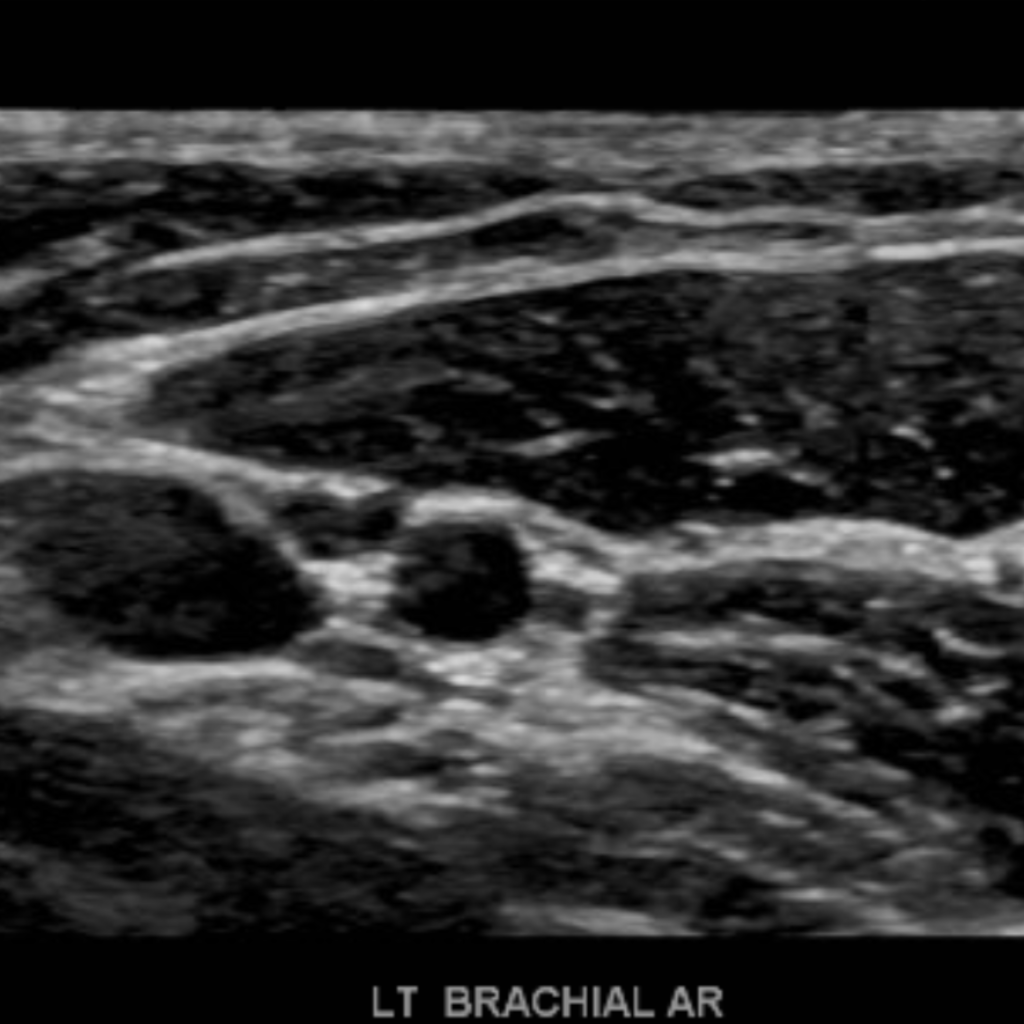

The subclavian artery arises from the brachiocephalic artery on the right and off of the aortic arch on the left. This artery further divides into the axillary, brachial, radial, ulnar, palmar and digital arteries respectively.